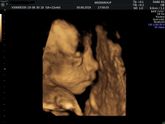

Всем привет! Была вчера на плановом приёме, по месячным срок 33,3 недель был, все у нас, Слава Богу, хорошо! Воды, плацента, кровотоки в норме! Головное предлежание.

НО… Вес ребенка 2760г! По УЗИ он на 35,5 недель. Но доктор сказал, что вообще не факт, … Читать далее